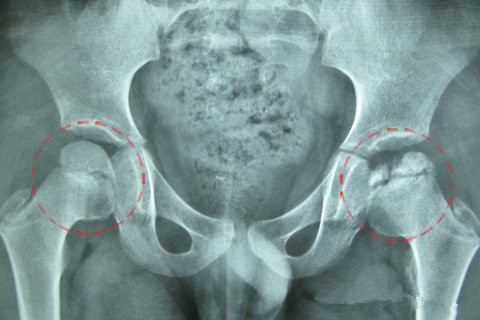

一、您了解股骨头坏死吗?股骨头坏死,又称股骨头无菌性坏死,是骨科…… 【详情】